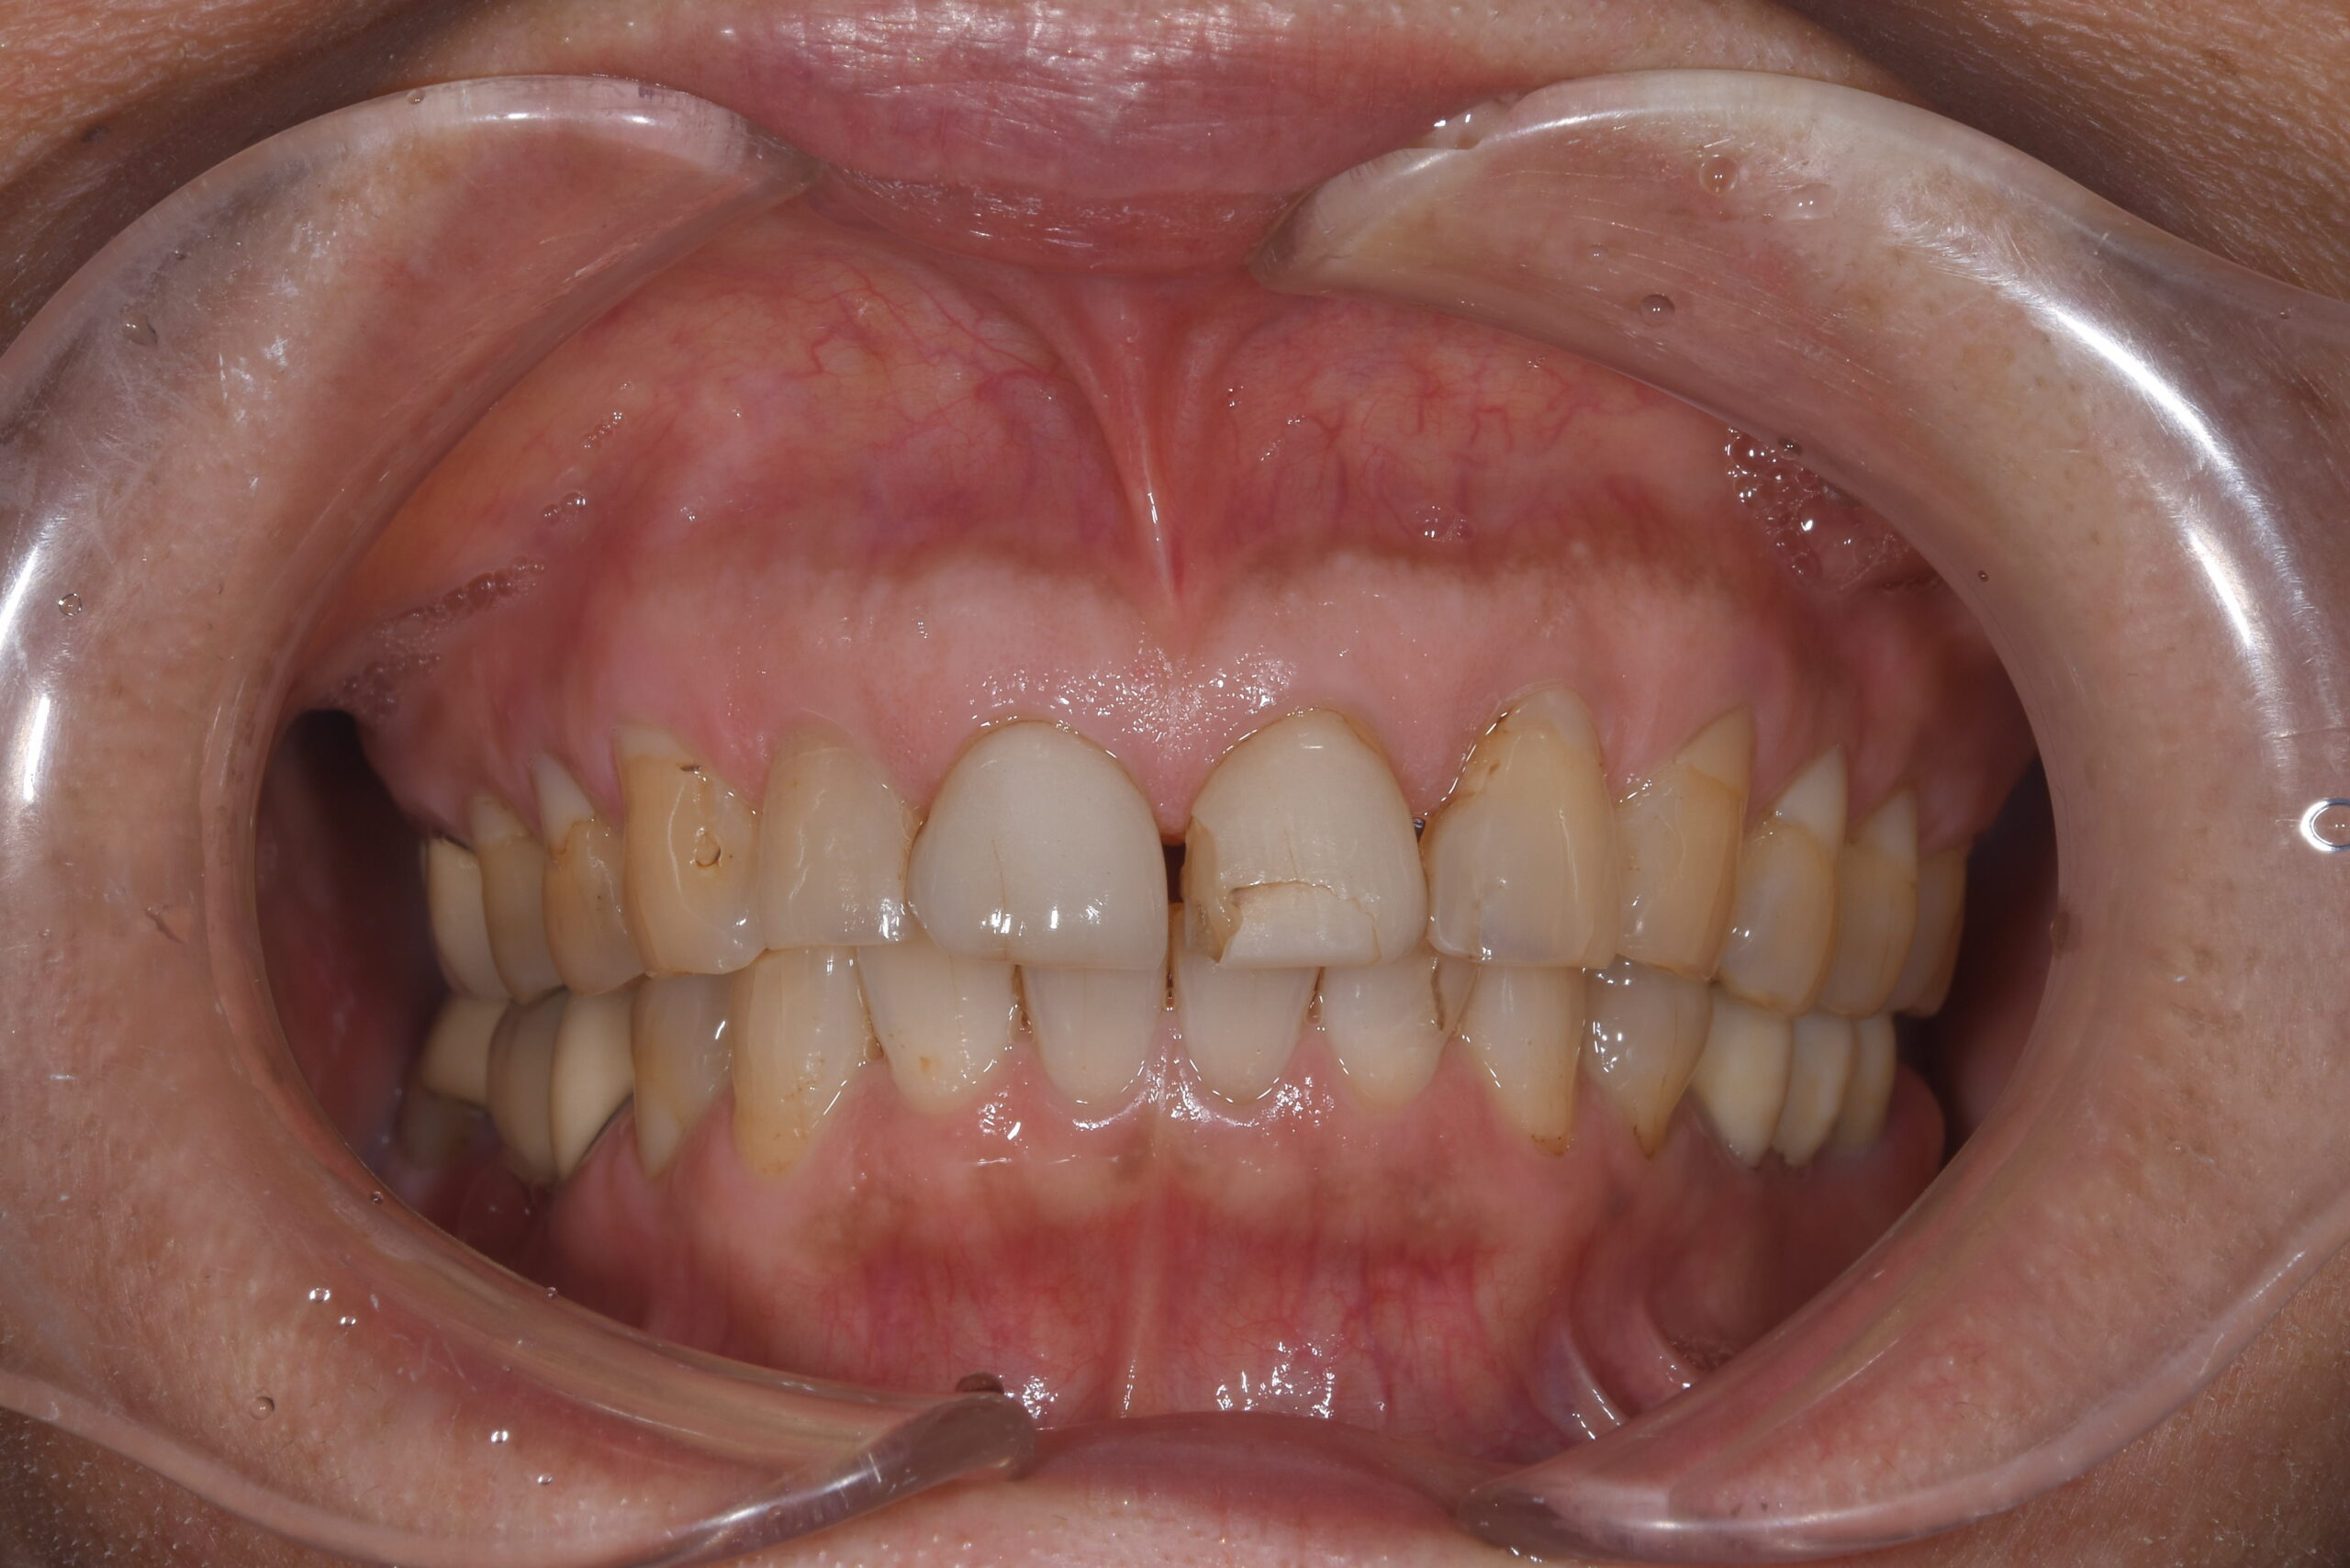

前歯が欠けた(60代)セラミック修復・ホワイトニング

年齢 67歳

性別 女性

初診日 2022年7月

主訴 審美障害

治療内容 セラミック修復・ホワイトニング

治療期間 4ヶ月

治療費用 約50万円

治療経過 前歯が欠けたとのことで来院された。

元々装着されていたラミネートベニアの破折であった。

ラミネートベニアのやり変えに合わせて、左側側切歯のサイズも小さくしたいとのご希望と歯の色も気にされていたため、ホワイトニングをした上で両側中切歯のラミネートベニアはクラウンにて、左側側切歯はラミネートベニアにて修復することとした。

神経にダメージが行かないよう注意深く形成し、仮歯とデジタルデザインにて形態をシミュレーションし、最終補綴物へと移行した。